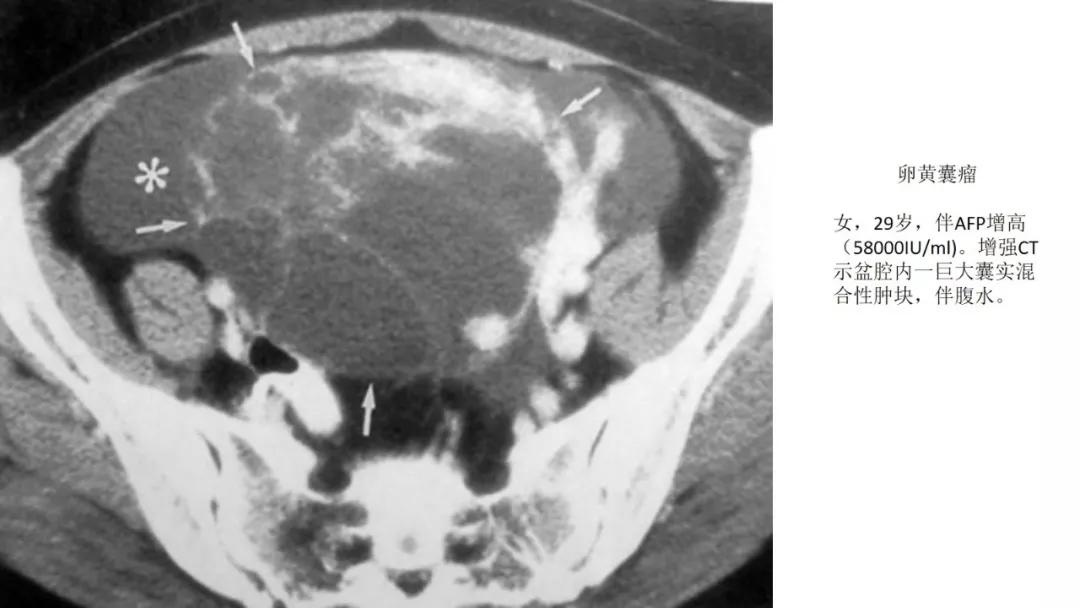

恶性者常呈实性或混杂性肿块,多数边界清楚,可伴有不规则沙粒状钙化。无性细胞瘤常为实性肿块,轻度强化,内胚窦瘤实性成分明显强化,不成熟畸胎瘤呈混杂密度。结合年龄及临床生化检查,有助于诊断。

AFP升高:卵黄囊瘤、无性细胞瘤、混合瘤

- 婴幼儿生殖细胞肿瘤中最常见的是卵黄囊瘤。